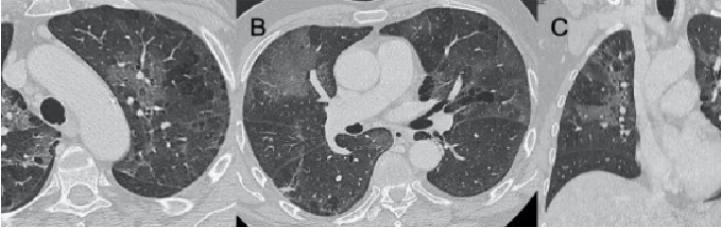

病毒性肺炎是由各种呼吸道病毒感染引发的肺实质炎症,容易并发呼吸衰竭,常见于幼儿(<5岁)和年龄>50岁的成人。WHO数据显示:社区获得性肺炎(CAP)中病毒性肺炎占20%~40%,在ICU中比例稍高,为30%~40%。常见病毒性肺炎的病原体包括流感病毒、鼻病毒、呼吸道合胞病毒、腺病毒、人偏肺病毒、巨细胞病毒、冠状病毒等。病毒性肺炎的常见影像学特征如下:图1所示为COVID-19的高分辨率CT(HRCT):在急性期,图1A为双肺弥漫性磨玻璃影(GGO),图1B为小叶周围型,图1C和D表现为亚急性间质性肺炎,GGO减少,主要为胸膜下局灶性实变和小叶间/小叶内间质增厚。图2A-C显示了一例与COVID-19间质改变相似的甲型流感病例:GGO主要分布在胸膜下和双侧,呈小叶周围性分布。图2D为同一患者的仰卧位胸片,可见弥漫性肺间质受累。图3A-D为一例H1N1相关肺炎并发急性呼吸窘迫综合征(ARDS)的影像,可见弥漫性、双侧GGO以及牵拉性支气管扩张。图4A显示了一例急性腺病毒肺炎,具有典型的多灶性和大叶GGO,图4B-C显示其导致的长期后遗症——Swyer–James综合征的表现。图5所示为一例疱疹病毒性肺炎,可见双侧分布呈斑片状的GGO(主要位于两肺上叶)。一项基于对美国大规模人群分析的前瞻性多中心研究显示,病毒性肺炎的患病率和发病率随年龄而异,其累积发生率约为22%。研究纳入2222例儿童,其中66%(共1472例)报告有病毒感染,在155例(7%)病例中发现病毒和细菌合并感染。事实上,呼吸道病毒、腺病毒和人偏肺病毒在5岁以下儿童中比较常见。在同一研究的2259例成年人患者中,只有853例(38%)患者检测到病原体,530例(23%)患有病毒性肺炎,59例(3%)发现合并感染。